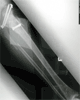

Post

Op

Xrays : alignment maintained with restoration of joint height